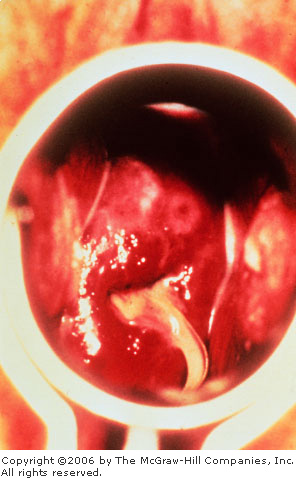

The patient's chief complaint is

often a purulent vaginal discharge. Speculum examination reveals a

purulent, viscous discharge emanating from the cervical os (Fig. 10.4).

Mucopurulent

Cervicitis Viscous, opaque

discharge emanating from the cervical os, consistent with

mucopurulent cervicitis. The string from an intrauterine device is

seen descending through the os in this patient. (Courtesy of Sue

Rist, FNP.)